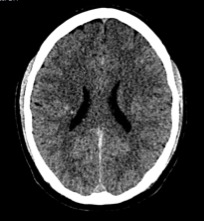

Ante un cuadro de déficit neurológico agudo la prueba de elección que se solicita es una TC cerebral, pues es la técnica ideal para realizar un cribado rápido de pacientes en los que requiere una evaluación rápida del tejido nervioso, se necesita agilidad y resolución inicial de la prueba. Se trata de un método diagnóstico fácil, accesible y disponible en la práctica totalidad de los servicios de urgencia hospitalarios, al contrario de lo que ocurre en la RM, una técnica lenta y muy costosa. Con la TC podemos obtener información detallada acerca de lesiones craneales como infartos, tumores y otras lesiones que no pueden ser diagnosticadas por la radiología simple.